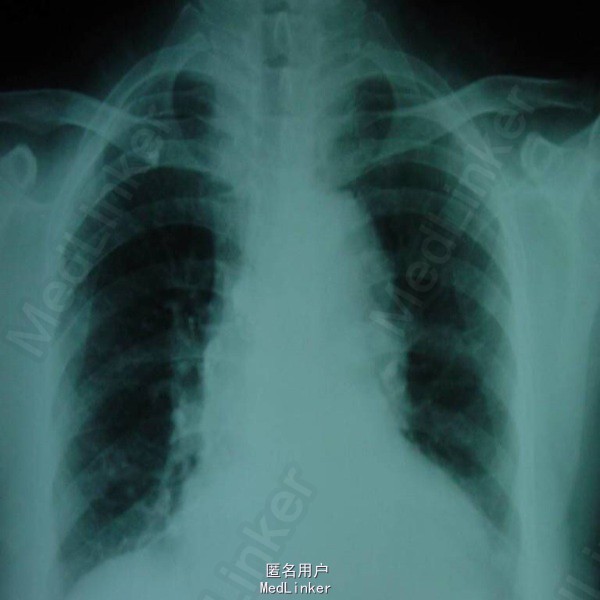

P 144次/分,R 65次/分,精神反应欠佳,面色发绀,呼吸急促,三凹征阳性,双肺呼吸音粗,可闻及中细湿罗音。心腹(-)。 血常规:WBC 6.8×10^9/L,HB 176g/L,N 0.62,L 0.33;CRP 80mg/L。胸片可见双侧肺纹理增多增粗,双下肺可见斑片状阴影。

诊断为:新生儿羊水吸入综合症 入院后予吸净羊水,予头孢曲松抗感染,吸氧及对症处理。患儿症状逐渐好转。10天后出院。